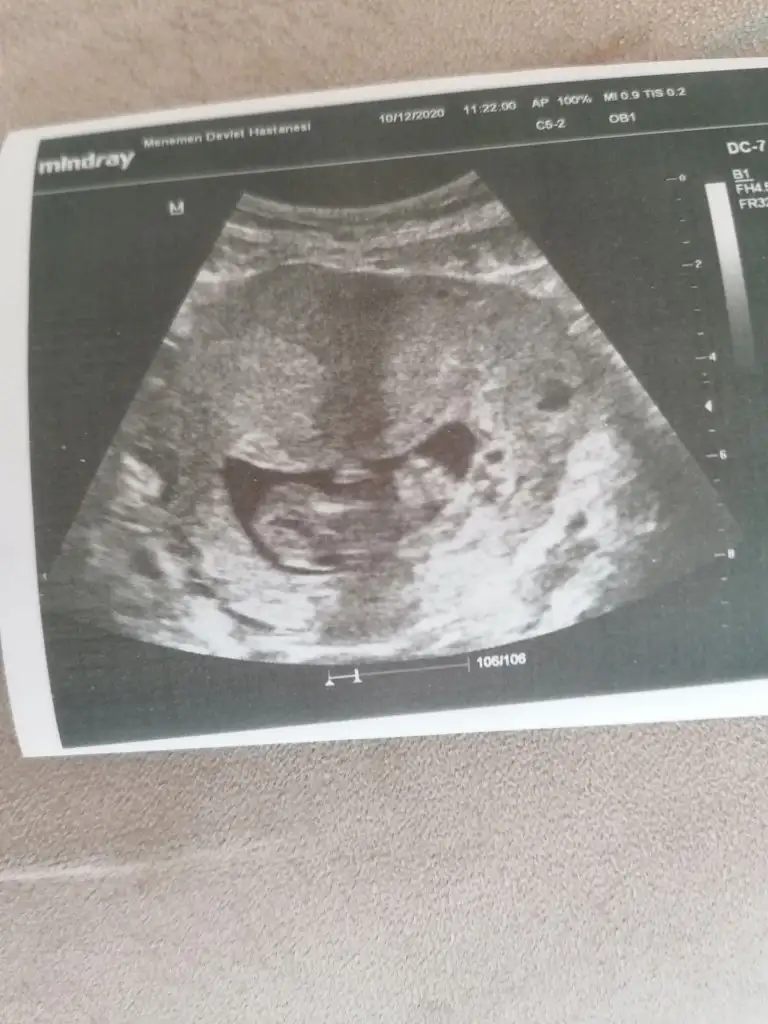

merhabalar banada yorum yapabilirmisiniz foto 12+4 tü şuan 15. haftadayım 2 oğlum var bu 3 cü olacak inşallah cinsiyetini çok merak ediyorum rabbim ilk önce sağlık versin

Ikra meyra Ikra meyra

Kız gibi emin olamadım başka USG varsa paylaşın 11 12 13 haftalar olmalı